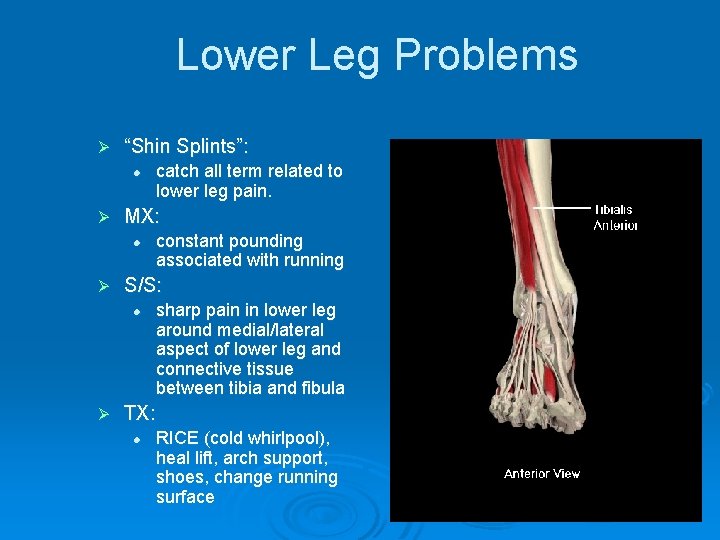

Lower Leg Problems Ø “Shin Splints”: l Ø MX: l Ø constant pounding associated with running S/S: l Ø catch all term related to lower leg pain. sharp pain in lower leg around medial/lateral aspect of lower leg and connective tissue between tibia and fibula TX: l RICE (cold whirlpool), heal lift, arch support, shoes, change running surface